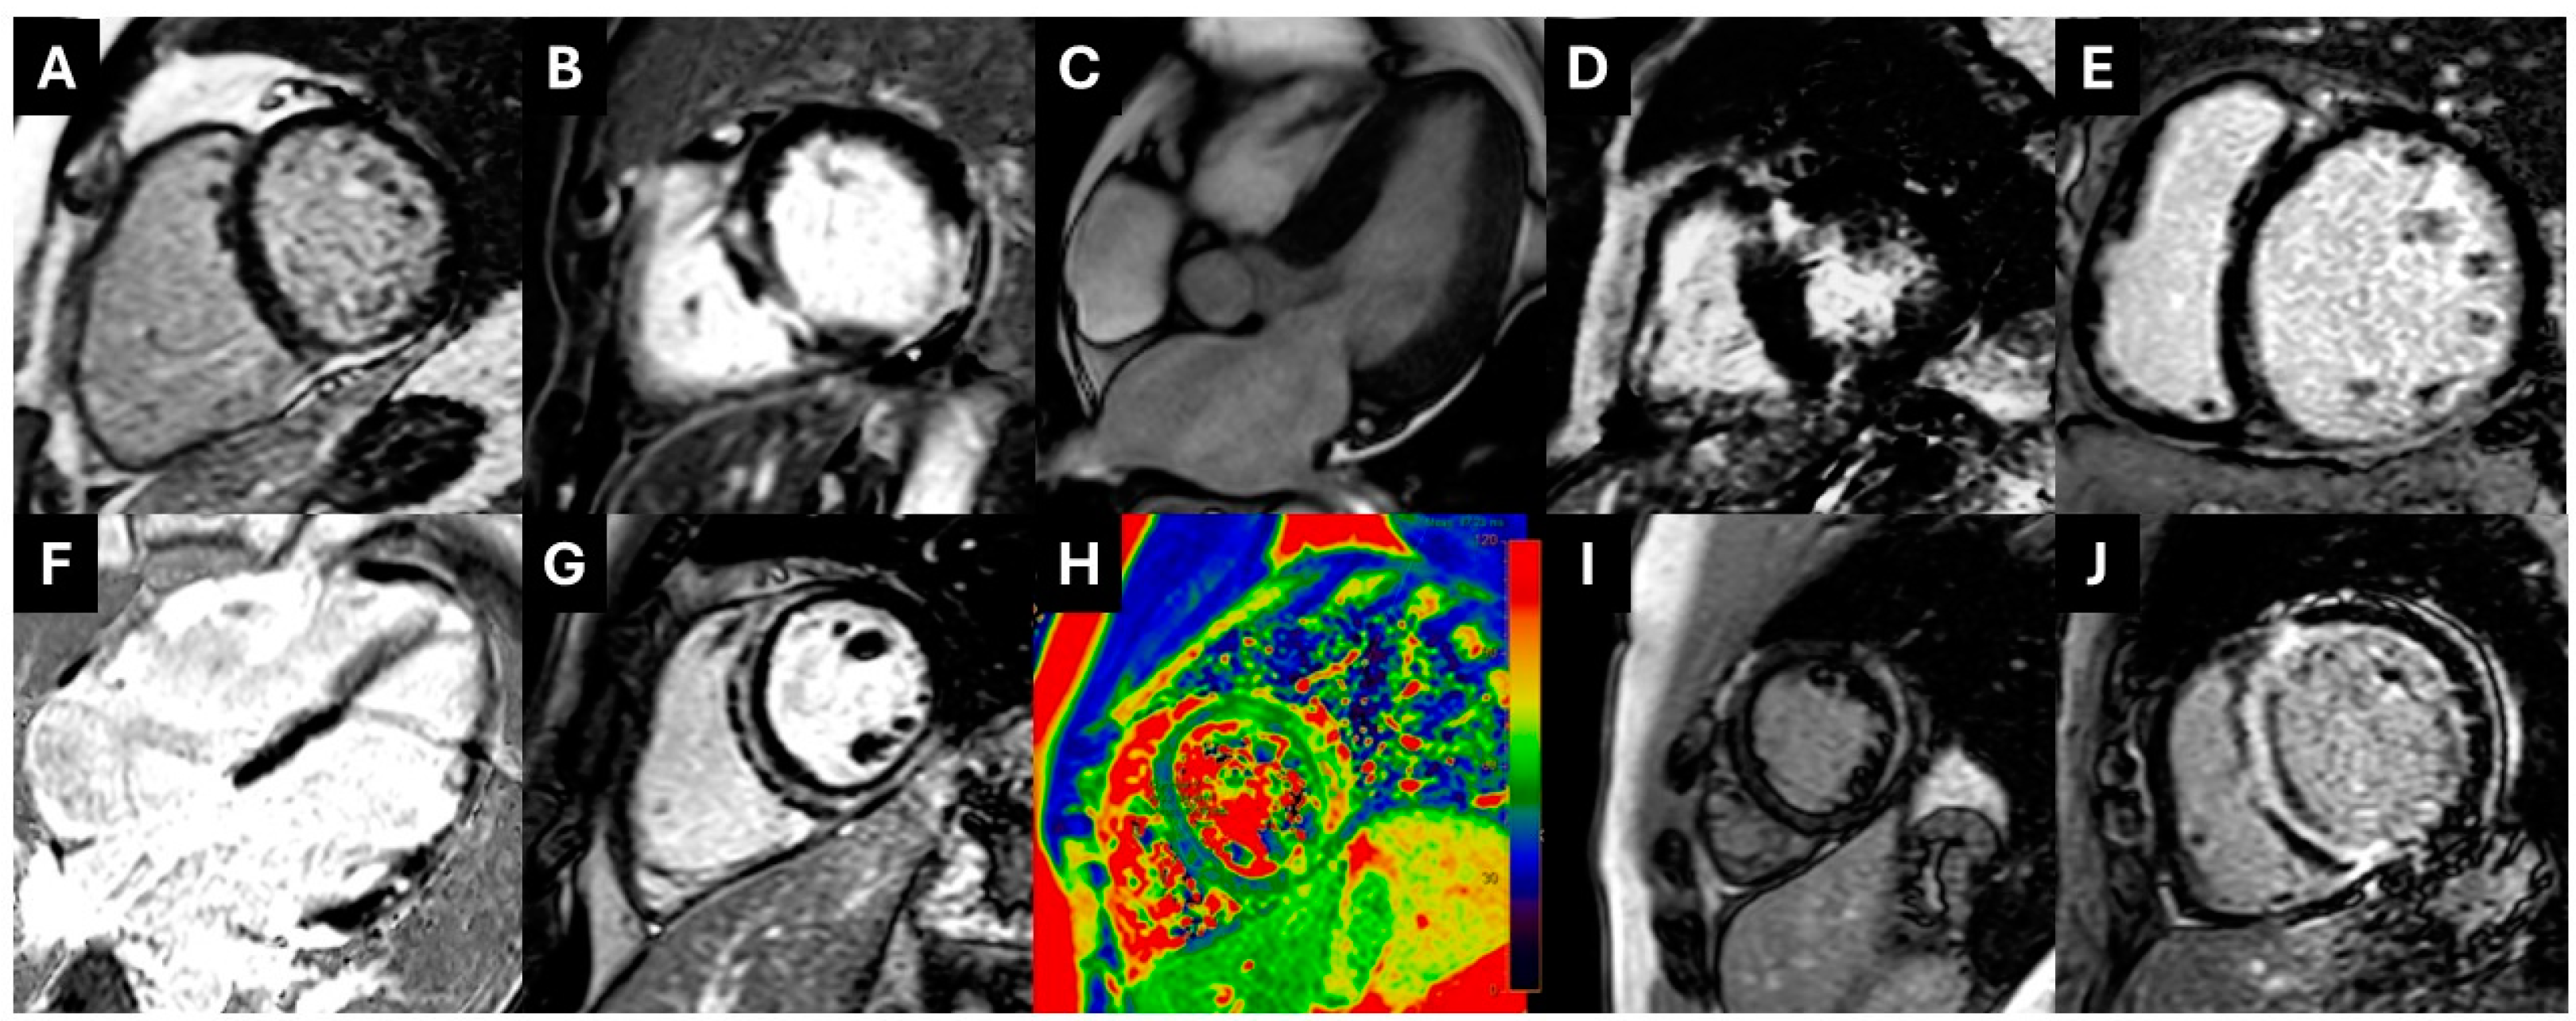

3.2. Clinical Diagnosis via CMR

3.3. Reclassification of Clinical Diagnosis via CMR